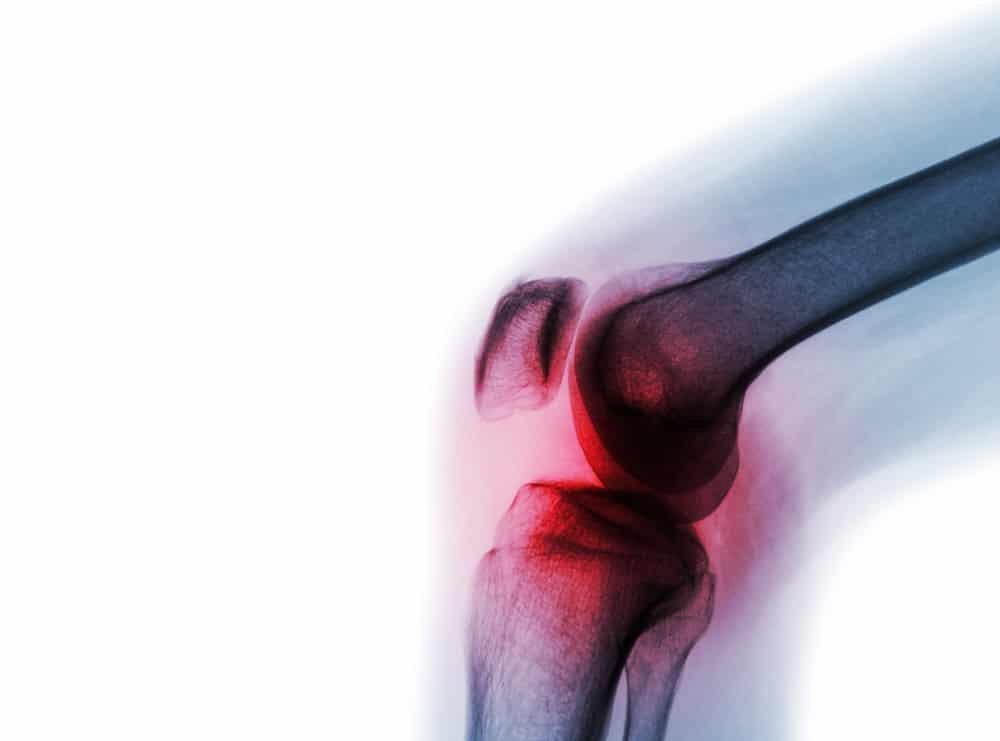

အဆစ်ရောင်နာ (Arthritis)

အဆစ်ရောင်နာ (Arthritis) ဆိုတာ အဆစ်တွေကို ထိခိုက်စေနိုင်တဲ့ ကျန်းမာရေးပြဿနာ တစ်မျိုးပါ။ အဆစ်တွေ နာကျင်တာ၊ ရောင်ရမ်းတာတွေ ဖြစ်စေနိုင်ပါတယ်။ လှုပ်ရှားဖို့ ခက်တာ၊ တက်တက်ကြွကြွနေဖို့ ခက်တာမျိုးတွေကိုလည်း ခံစားရနိုင်ပါတယ်။ အဆစ်ရောင်နာတွေက အမျိုးမျိုးပါပဲ။ တစ်မျိုးစီတိုင်းမှာ မတူညီတဲ့ လက္ခဏာတွေ ခံစားရနိုင်ပါတယ်။ အဆစ်ရောင်နာ အမျိုးအစားကို လိုက်ပြီး ကုထုံးတွေလည်း ကွာခြားနိုင်ပါတယ်။ အဆစ်ရောင်နာ က များသောအားဖြင့် အသက်အရွယ် ကြီးရင့်သူတွေမှာ အဖြစ်များပါတယ်။ အမျိုးသားတွေမှာ ဖြစ်နိုင်သလို အမျိုးသမီးတွေ၊ ကလေးတွေမှာလည်း ဖြစ်နိုင်ပါတယ်။ အရွယ်သုံးပါးစလုံး ခံစားရနိုင်တဲ့ ကျန်းမာရေး ပြဿနာပါ။ အဆစ်ရောင်နာ (Arthritis) ဆိုတာ အဆစ်ရောင်နာ ဆိုတာ အဆစ်တွေ ( အရိုး တစ်ခုခုနဲ့ တစ်ခု ဆုံပြီး လှုပ်ရှားမှုတွေ လုပ်ဆောင်နိုင်တဲ့ နေရာ) မှာ ထိခိုက်စေတဲ့ ကျန်းမာရေး […]